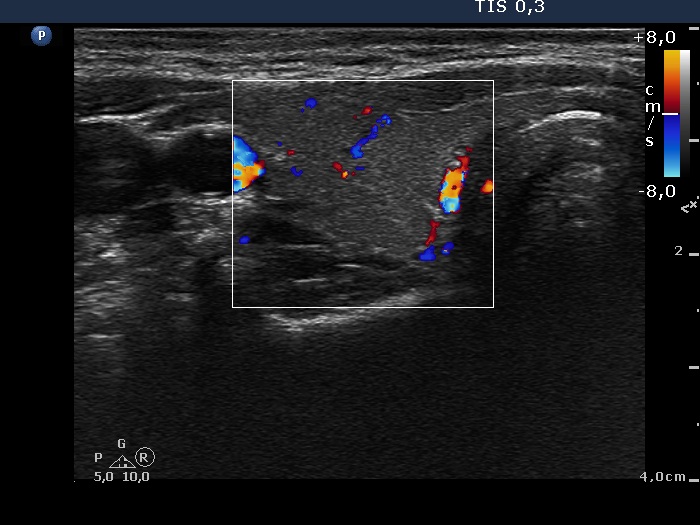

Ultrasonography. The thyroid was echonormal and contained a minimally hypoechogenic nodule in the ventral part of the right lobe. There was a cystic lesion under the lower pole of the left lobe.

Cytology of the thyroid lesion resulted in benign colloid goiter. 16 mL watery fluid was aspirated from the mass under the thyroid. Wash-out parathormone level of the cystic fluid was 917 pg/mL, while serum parathormone was 24.3 pg/mL (normal value: 15-65).